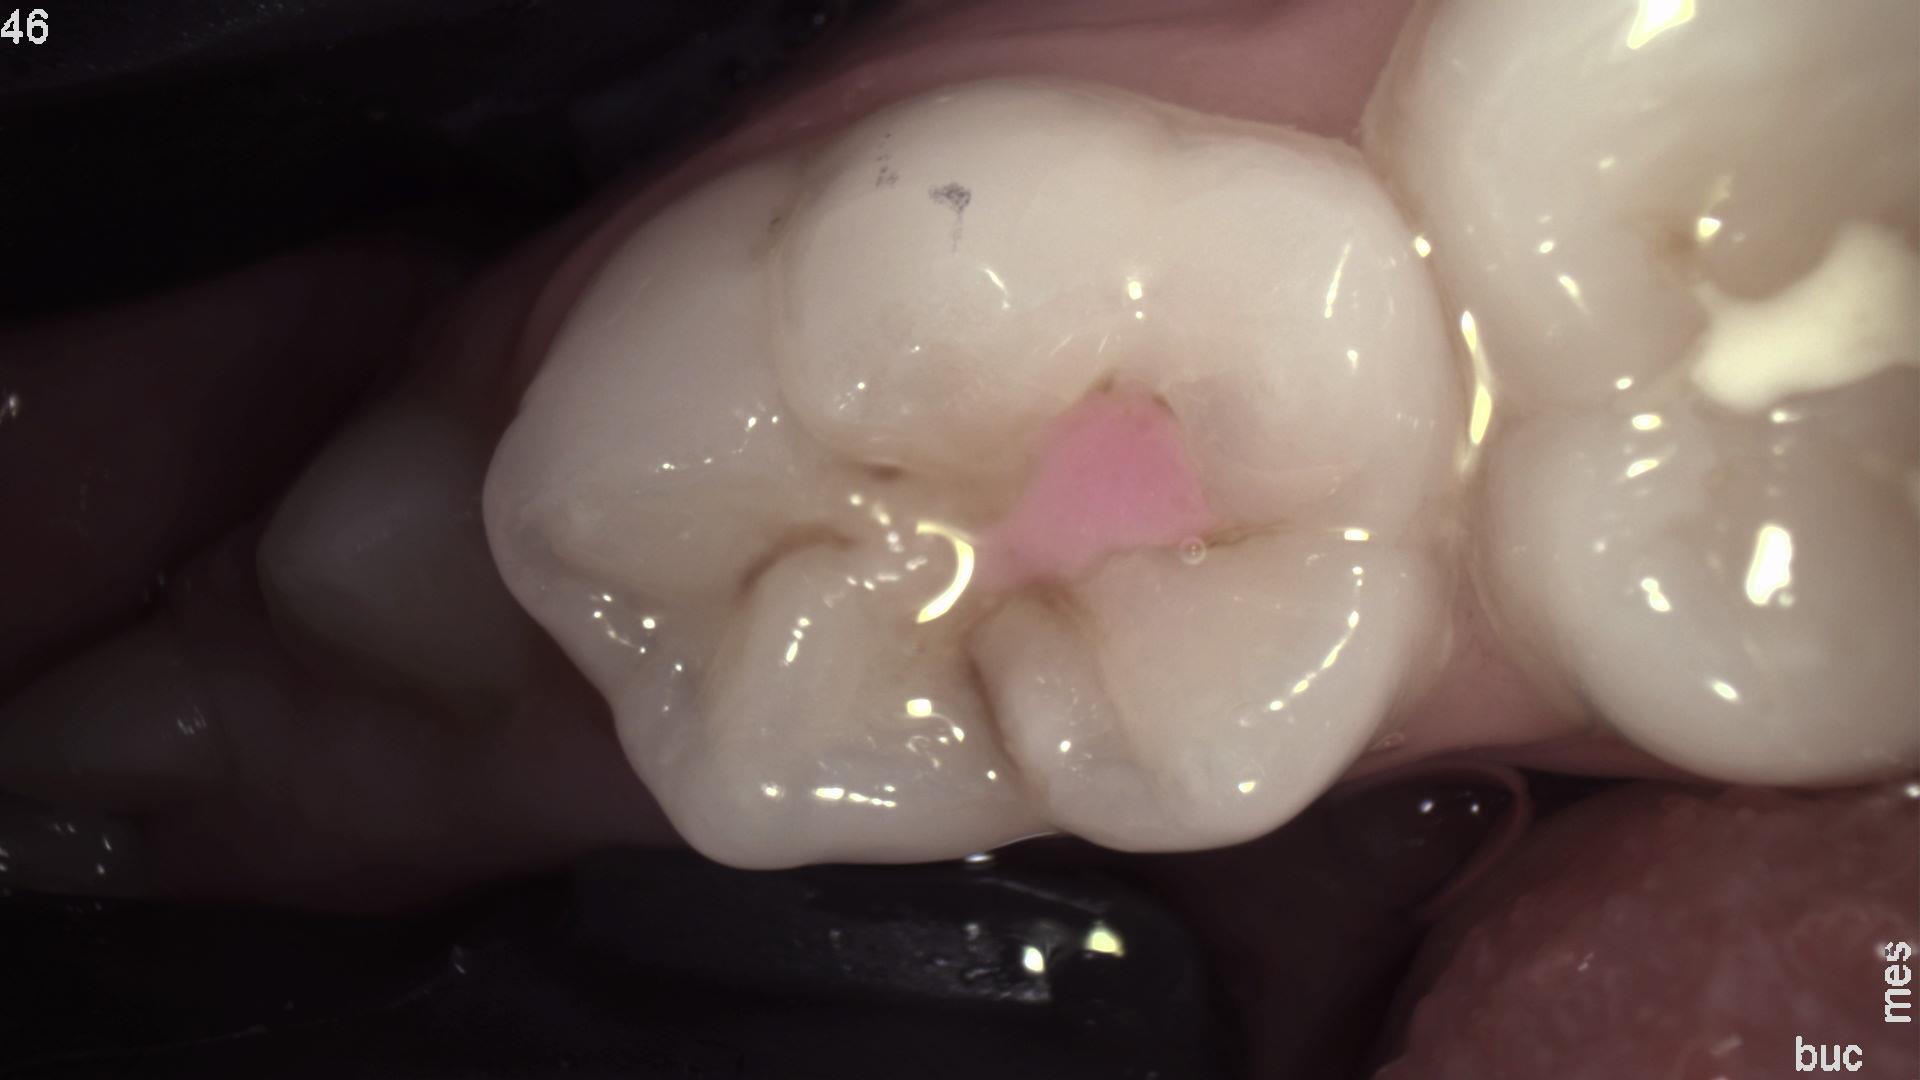

Pierwsze z trzech wykonanych jednocześnie zdjęć stałego zęba trzonowego przy pomocy DIAGNOcam z wykorzystaniem kamery rejestrujące światło widzialne. Ten obraz jest najbardziej czytelny dla pacjenta.

Takie potrojone obrazowanie pozwala na dokładną diagnostykę zmian próchnicowych, ewentualnej obecności płytki bakteryjnej na powierzchni zębów oraz prezentację wyników diagnostycznych pacjentom w sposób nie budzący żadnych wątpliwości. Cały proces badania realizowany jest tym samym urządzeniem, podłączonym do komputera i monitora. Lekarz dostaje do dyspozycji trzy obrazy: diagnostyczny z kamery IR (najbardziej mu potrzebny), rzeczywisty z kamery wewnątrzustnej (najbardziej trafiający do pacjenta), oraz fluorescencyjny (najbardziej motywujący do leczenia i poprawy higieny), a wszystkie obrazy mają dokładnie tą samą projekcję i łatwo je ze sobą porównać. Technologia NILT umożliwia wykonanie prześwietlenia zęba i zdiagnozowanie zmian próchnicowych o każdym stopniu zaawansowania.